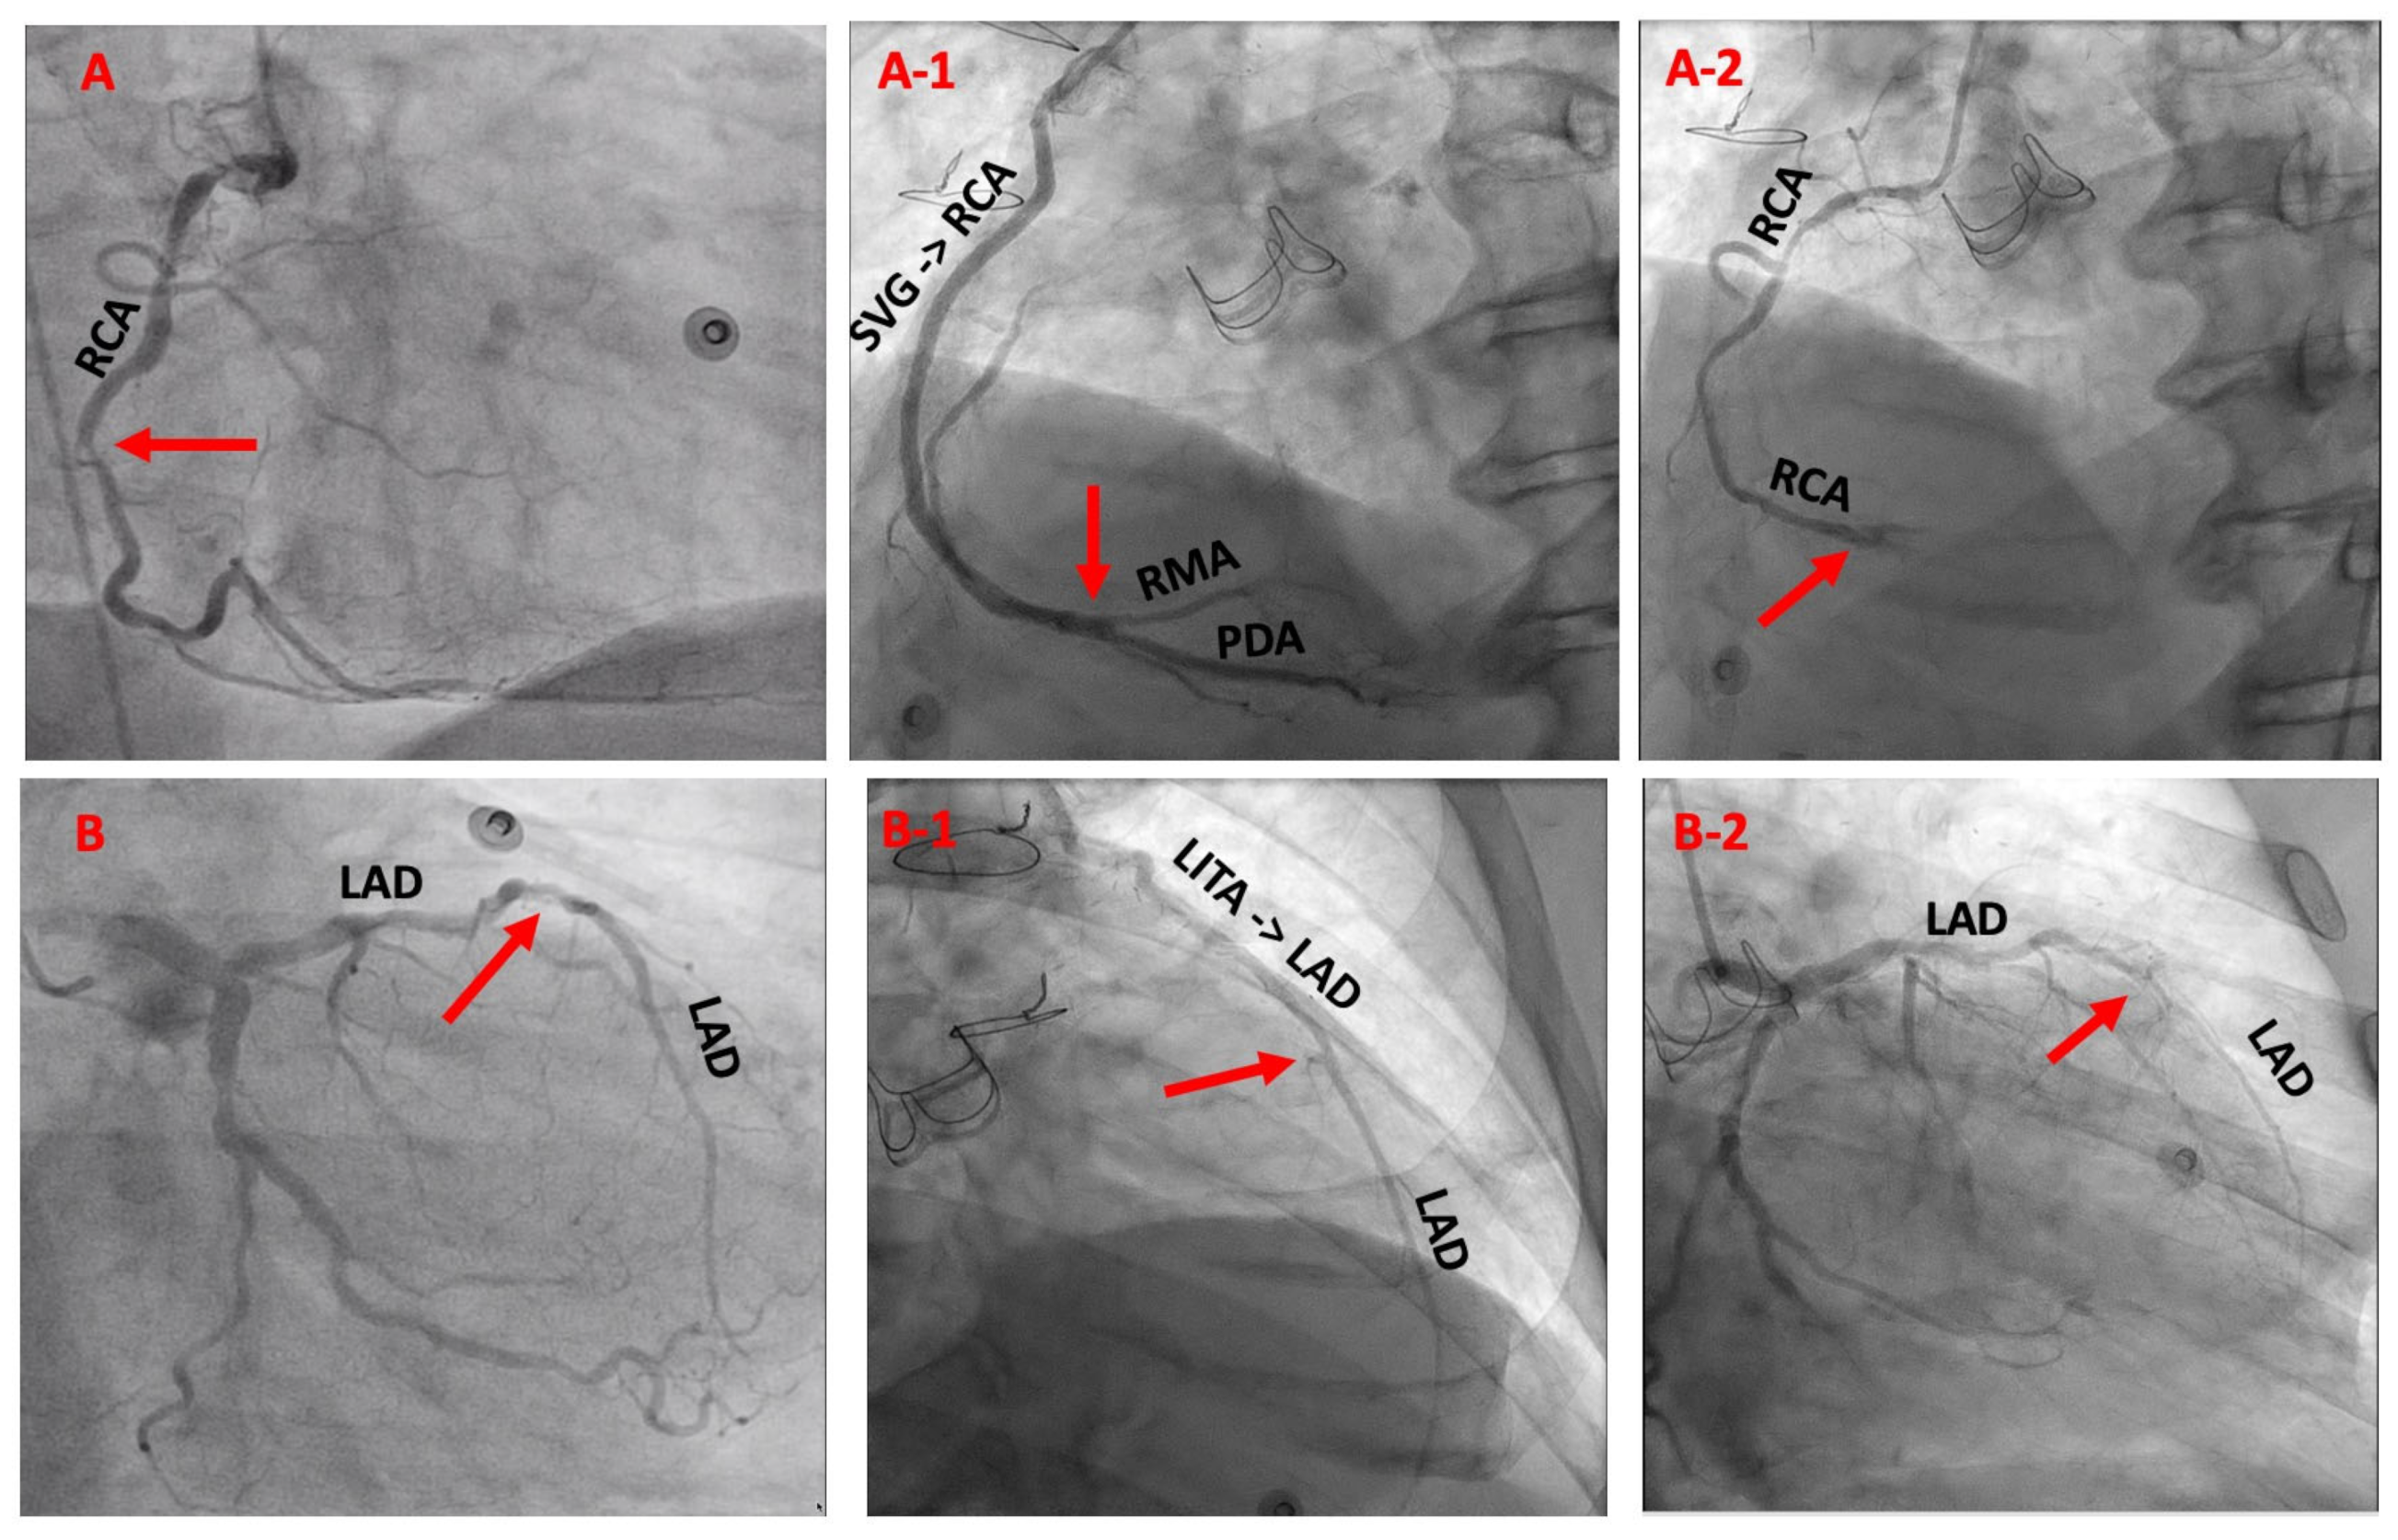

- Shehada, S.E.; Mourad, F.; Balaj, I.; El Gabry, M.; Wendt, D.; Thielmann, M.; Schlosser, T.; Jakob, H. Long-Term Outcomes of Coronary Endarterectomy in Patients with Complete Imaging Follow-up. In Seminars in Thoracic and Cardiovascular Surgery; Elsevier: Amsterdam, The Netherlands, 2019. [Google Scholar] [CrossRef]